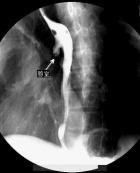

食管憩室(diverticulum of oesophagus)系指與食管相通的囊狀突起。其分類比較繁雜。按發(fā)病部位可分為咽食管憩室、食管中段憩室和膈上食管憩室。根據(jù)其發(fā)病機(jī)制不同又分為牽引性、內(nèi)壓性、牽引內(nèi)壓性憩室。根據(jù)憩室壁的構(gòu)成可分為真性憩室(含有食管壁全層)和假性憩室(缺少食管壁的肌層)。此外尚可分為先天性憩室和后天性憩室。